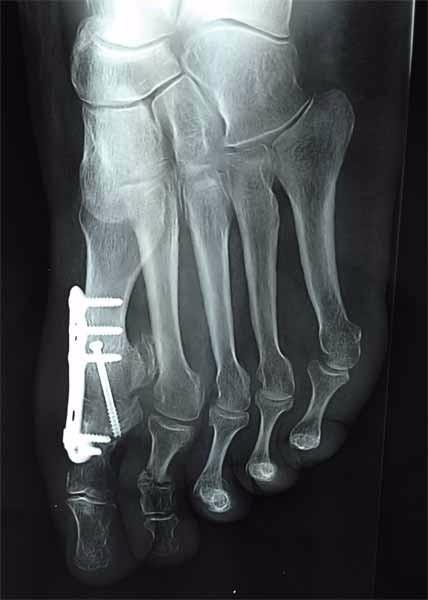

Dans un premier temps le traitement est médical : prescription d’antalgiques et d’anti-inflammatoires, le port permanent d’une semelle rigide. Ensuite, si la chirurgie s’avère nécessaire, votre médecin procédera alors au blocage de l’articulation par arthrodèse.